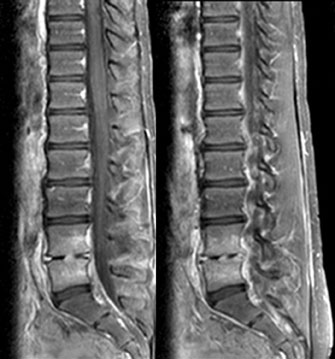

ΔΙΣΚΙΤΙΔΑ

Παιδί 11 χρόνων με άλγος στη δεξιά οσφυική χώρα, χωρίς άλλα κλινικά ευρήματα και με αυξημένη ΤΚΕ (111). Ιστορικό πτώσεως προ 8 μηνών κατά τη γυμναστική.

Τέθηκε η διάγνωση δισκίτιδας και με δεδομένο ότι συχνότερο αίτιο είναι ο σταφυλόκοκκος, το παιδί έλαβε IV κλινδαμυκίνη και κεφτριαξόνη για 1 εβδομάδα και κλινδαμυκίνη από το στόμα για 7 εβδομάδες.

Η πορεία του ήταν καλή και ουσιαστικά ιάθηκε.